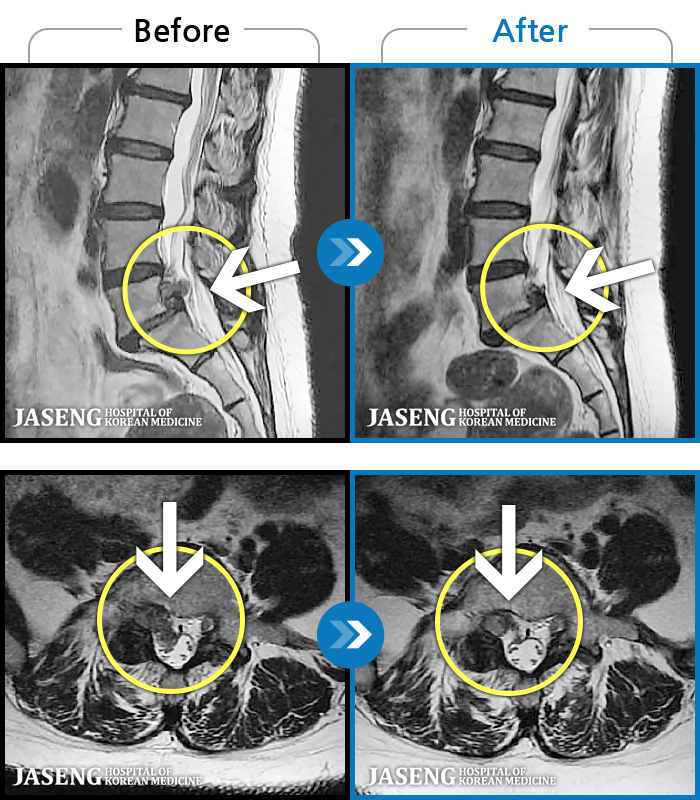

MRI ġ

119 MRI ũ ʸ Ȯϼ.

[Կñ:22.08.30~24.08.05]

[_㸮ũ] ٸ ߳ .

No.118

ȸ 505

2024.12.24